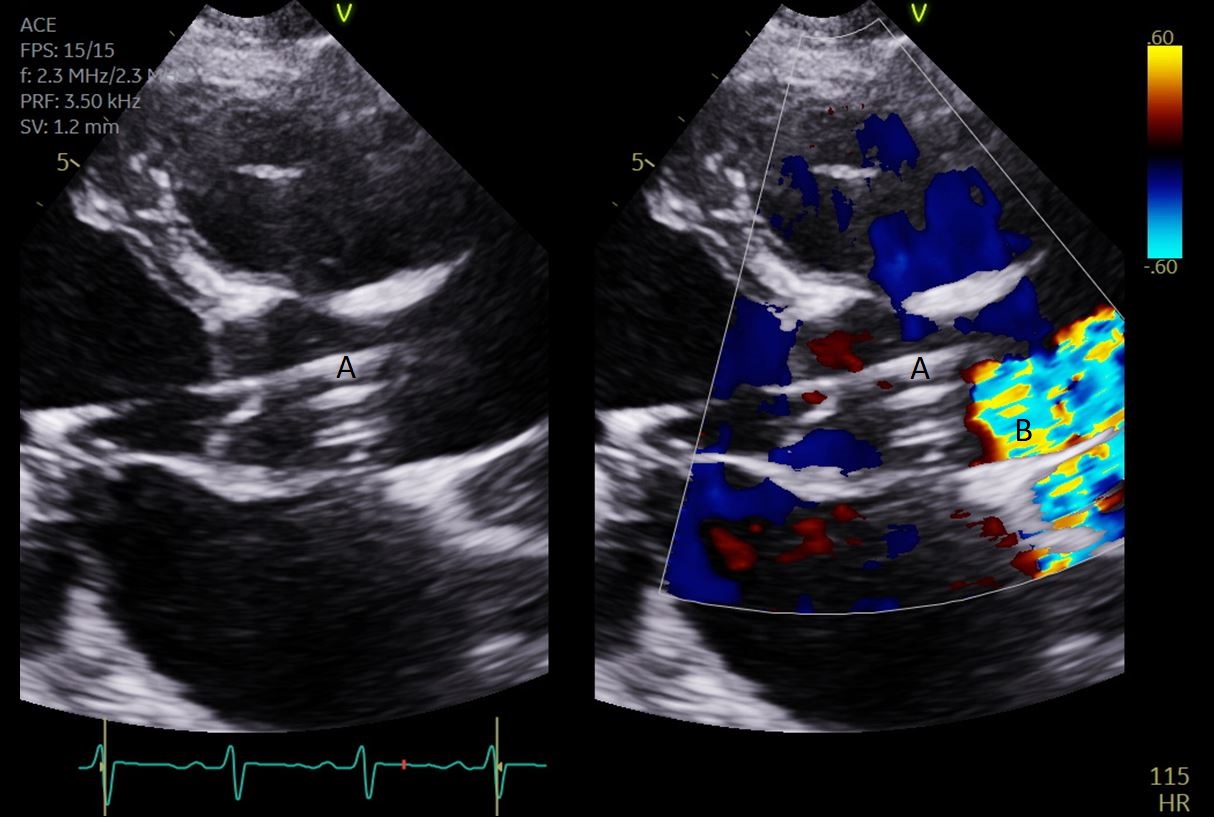

The intra-aortic balloon pump is a percutaneously placed counter pulsation device which helps in decreasing afterload as well as augmenting coronary perfusion. Initially developed in the 1960s it is the oldest MCS device and given its simplicity, cost effectiveness, and ease to implant and explant, it is the most commonly used temporary support device [6]. Although it is typically placed in the cardiac catheterization lab under fluoroscopic guidance, TEE can be utilized to help in its placement in the intubated patient in the intra-operative setting. The femoral artery is the most common site of placement however they can on occasion be placed in alternative sites such as the axillary artery or directly into the aorta [7, 8]. When placed via the femoral artery, it is threaded over a guidewire. TEE can be used to visualize both the guidewire as well as the tip of the IABP catheter during placement (Fig. 1) [9]. Ideal positioning of the balloon tip is 1–2 cm distal to the left subclavian artery to derive maximal hemodynamic benefit [10]. Positioning can be confirmed by visualizing the descending aorta and then withdrawing the TEE probe until the left subclavian artery and aortic arch are visualized. Upon activation of the balloon pump the gas filled balloon will cause shadowing and reverberation artifacts (Fig. 2). Its presence can be used as confirmation of proper function of the device. If these artifacts are not seen or bubbles are visualized in the aorta, rupture of the IABP should be suspected [9]. In addition to hemodynamic monitoring with a Swan-Ganz catheter, TTE can be used to monitor LV function after IABP placement and can help guide weaning of IABP support. It can also visualize any new or worsening aortic regurgitation. Given that IABPs work by reducing afterload, on rare occasions they can precipitate dynamic outflow tract obstruction and paradoxically worsen cardiogenic shock. Examples include patients with a relatively preserved basal or septal myocardial function in scenarios such as takotsubo cardiomyopathy or acute myocardial infarctions. Doppler imaging and color flow doppler can be used to identify such scenarios [11].

Fig. 1.TEE demonstrating IABP in descending aorta (A).

TEE demonstrating IABP in descending aorta (A) with reverberation artifact seen behind it upon activation (B).